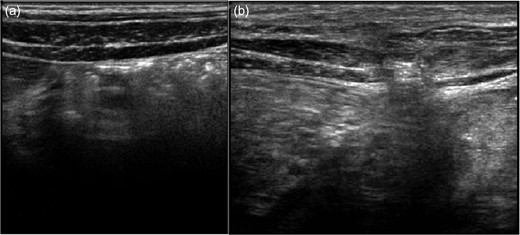

The physical examination revealed the presence of a painless swelling measuring 8 × 3 cm2 and did not reveal any pathological sign from the abdomen. The swelling was reducible, disappeared in supine position and increased by coughing. The diagnosis of a HH was suspected and confirmed by ultrasound that showed the disruption of internal and external oblique and transverse muscle (6 × 1.5 cm2) and the projection of omentum through the hernia without other associated internal organ injuries (Fig. 2). The hematological and biochemical tests were normal. We suggested the admission of the child in our clinic for further clinical monitoring but the parents denied.

Ultrasound images of the right (a) and left (b) side of the abdominal wall at the time of admission. Left side: disruption of internal and external oblique and transverse muscles and projection of omentum.